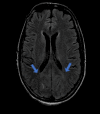

Figure 4

Figure 4. MRI brain showing few areas of diffusion restriction which were of low intensity on the ADC map on the left side with gyriform pattern

ADC: apparent diffusion coefficient